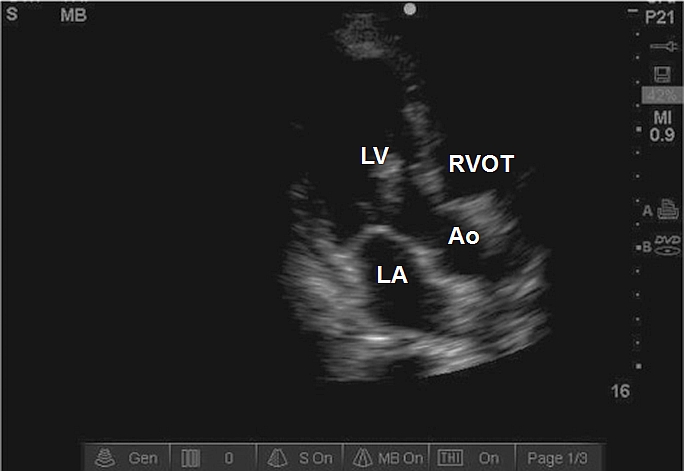

Case 7-1. Parasternal Long-axis View

Video 7-1A. This video demonstrates the importance of performing the initial view with a depth setting that allows visualization of structures posterior to the heart. In this case, there is a pleural effusion with atelectatic lung floating within it. This would be missed if the depth setting were set initially to place the heart in central screen position.

Video 7-1B. Depth setting adjusted to place the heart in central screen position. There is severe reduction of left ventricular (LV) function with a segmental wall abnormality involving the anterior septum. The septum is thin and the LV cavity is dilated suggesting chronic LV dysfunction related to ischemic injury. Diastolic excursion of the anterior mitral valve (MV) is reduced consistent with reduced LV function. Chamber size and wall thickness would require formal measurement with M-mode or direct caliper measurement.

Video 7-1C1. Color Doppler interrogation of the mitral valve with what is likely moderate mitral regurgitation (MR). The examiner is required to enlarge the color grid to cover the entire left atrium in order to give an more accurate qualitative estimate of the severity of the MR. The cause of the MR is not evident by morphological pattern, while the segmental wall abnormality suggests the possibility of ischemic origin.